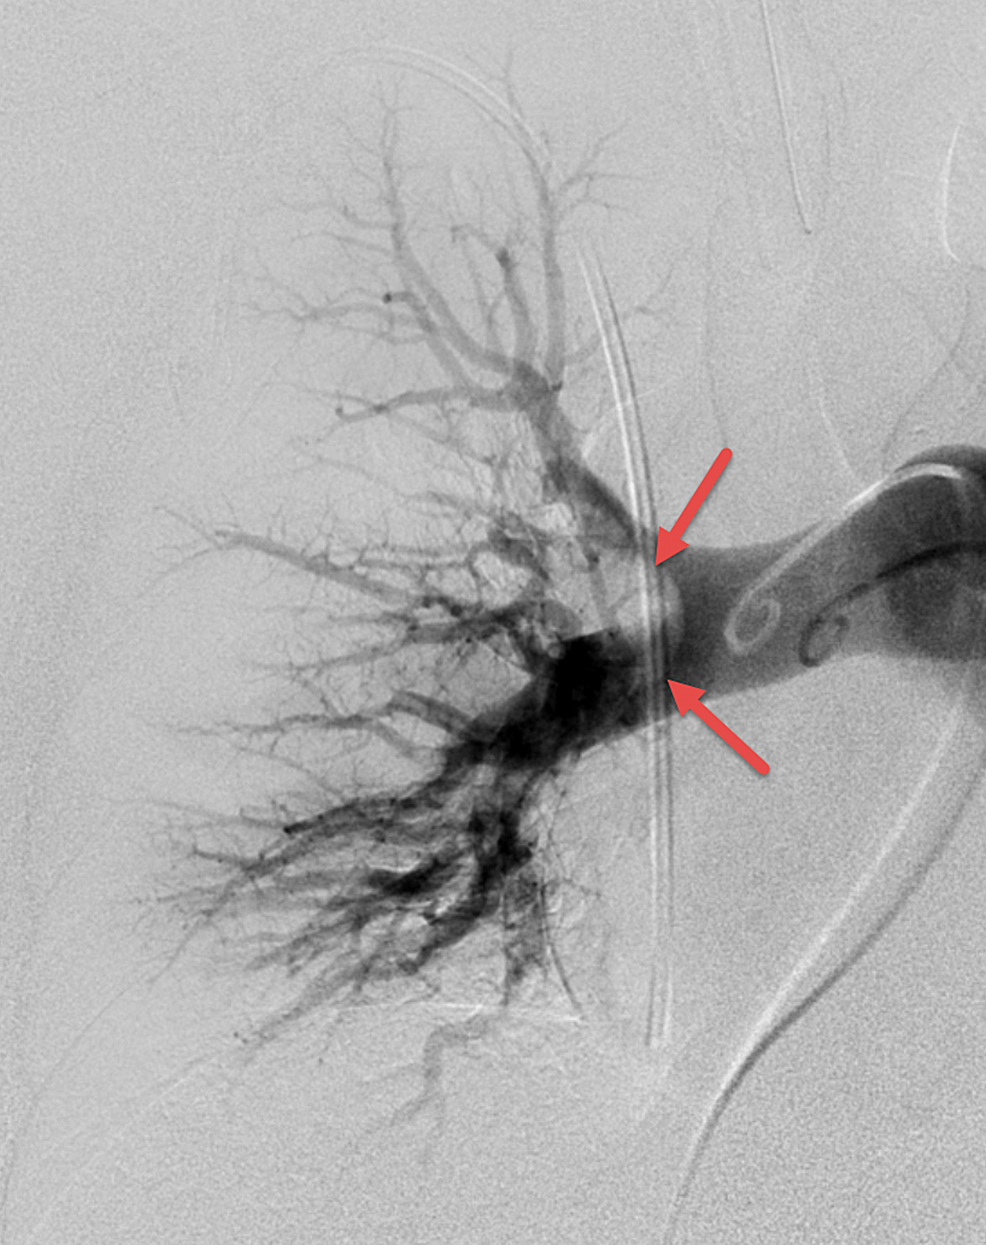

Catheterdirected mechanical aspiration thrombectomy procedure. (A Pulmonary Thrombectomy Anesthesia Surgery puts patients at increased risk for pulmonary embolism (pe). This section provides a comprehensive procedural report for pulmonary artery thrombectomy and thrombolysis. This operation leads to major clinical improvement and is a potential cure for a large majority for patients suffering from cteph [1]. The purpose of this narrative review is to provide guidance to anesthesiologists for the assessment. Pulmonary Thrombectomy Anesthesia.